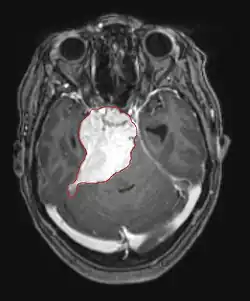

La tomodensitométrie (TDM) et L'imagerie par résonance magnétique (IRM) peuvent détecter efficacement une néoplasie dans le cerveau. L'IRM est plus sensible que la TDM pour identifier les lésions, mais présente des contre- indications pour les patients porteurs de stimulateurs cardiaques, de prothèses incompatibles, de clips métalliques et contre-indications. La TDM reste la méthode de choix pour détecter les calcifications au sein des lésions ou les érosions osseuses de la calotte ou de base du crâne. L'utilisation d' agents de contraste, iodés dans le cas du scanner et paramagnétiques (gadolinium) dans le cas de l'IRM, permet l'acquisition d'informations sur la vascularisation et l'intégrité de la barrière hémato-encéphalique, une meilleure définition de la tumeur tumorale par rapport à l' œdème environnant et à la génération d' hypothèses sur le degré de malignité. L'examen radiologique permet également d'évaluer les effets mécaniques et les modifications importantes des structures cérébrales résultant de la tumeur, telles que l' hydrocéphalie et les hernies, dont les effets peuvent être fatals. Enfin, en préparation à la chirurgie, ce diagnostic peut être utilisé pour déterminer la localisation de la lésion ou l'infiltration de la tumeur dans des zones vitales du cerveau. À cette fin, l'IRM est plus efficace que la tomodensitométrie car elle peut fournir des images en trois dimensions.

Les outils d'imagerie radiologique diagnostique mettent en évidence la modification du tissu néoplasique par rapport au parenchyme cérébral normal (par le biais de modifications de la densité tissulaire imagée électroniquement en TDM et de l'intensité du signal en IRM). Comme la plupart des tissus pathologiques, les tumeurs sont également reconnaissables par une accumulation accrue d'eau intracellulaire. Dans la tomodensitométrie, ils apparaissent hypodenses, c'est-à-dire de moindre densité que le parenchyme cérébral, dans la tomographie par résonance magnétique nucléaire avec relaxation spin-réseau hypointense et en relaxation spin-spin ainsi que l' hypersignal en pondération protonique (PD).

Dans le tissu tumoral, en général, la plus grande proportion d'amélioration du contraste est due à la barrière hémato-tumorale particulière qui permet le passage de l'iode (CT) et du gadolinium (IRM) dans l'espace interstitiel extravasculaire intratumoral. Cela augmente le signal (densité ou intensité) de la tumeur. Cependant, des précautions doivent être prises pour s'assurer que l'amélioration du contraste ne différencie pas définitivement la néoplasie de l'œdème péri-lésionnel. En fait, la découverte anatomo-pathologique dans le tissu tumoral infiltrant malin du gliome, comme dans le glioblastome et l'astrocytome anaplasique, montre également au-delà de l'œdème vasogénique causé par la destruction de la barrière hémato-encéphalique par la tumeur. Cette dernière condition clinique est difficilement détectable par imagerie diagnostique.

Sur-L'IRM montre une tumeur intracrânienne comme une lésion massive qui peut devenir plus luminescente après utilisation du produit de contraste. Cependant, il y a toujours une anomalie de signal dans -L'imagerie par résonance magnétique, qui indique la présence d'une néoplasie ou d'un œdème vasogénique. Habituellement, une luminescence accrue (amélioration du contraste) indique une tumeur d'un grade supérieur de malignité. Un anneau de contraste est caractéristique du glioblastome, avec la partie luminescente correspondant à la partie vitale de la tumeur maligne, et la plus foncée - zone hypointense correspondant à une nécrose tissulaire.

Les métastases cérébrales sont les néoplasmes intracrâniens les plus courants chez les adultes, étant dix fois plus fréquents que les tumeurs cérébrales primaires. Ils marchent à 20 jusqu'à 40 pour cent des adultes atteints de cancer et sont principalement associés au cancer du poumon et du sein et au mélanome . Ces lésions résultent de la propagation des cellules cancéreuses dans la circulation sanguine et surviennent le plus souvent à la jonction de la matière grise et blanche, où la section transversale des vaisseaux sanguins change, emprisonnant les embolies de cellules tumorales . 80 % des lésions surviennent dans les hémisphères cérébraux, 15 pour cent dans le cervelet et 5 pour cent dans le tronc cérébral. Environ 80 % des patients ont des antécédents de cancer systémique et 70 pour cent ont de multiples métastases cérébrales.

Des progrès significatifs ont récemment été réalisés dans le diagnostic et le traitement de ces lésions, entraînant une amélioration de la survie et du contrôle des symptômes. L'apparition des signes et des symptômes est similaire à celle d'autres lésions massives du cerveau. La méthode de diagnostic de choix est l'imagerie par résonance magnétique utilisant des produits de contraste.